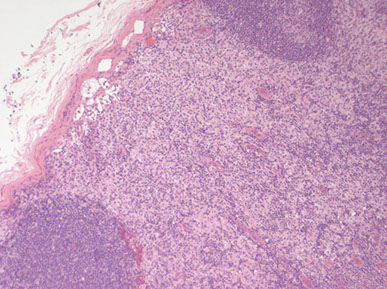

Syphalitic lymphadenitis [3]. Florid follicular hyperplasia with back-to-back appearance with little paracortex (may raise suspicion for malignancy), although the follicles have some degree of polarization. The capsule is intact, and appears thickened. There is some variability in the size and shape of the follicles (though that is a soft sign because can be seen in some low-grade follicular lymphomas). Plasma cells in the follicles in reactive GCs and in the thickened capsule.

Syphilis can have marked plasmacytosis, which is polytypic, can even have high IgG4 to IgG ratio, but IHC should reveal the organisms [3]

Syphilis. Areas with markedly-expanded paracortex with mix of lymphocytes, histiocytes, neutrophils, and sclerosis.

Also syphilis [3]